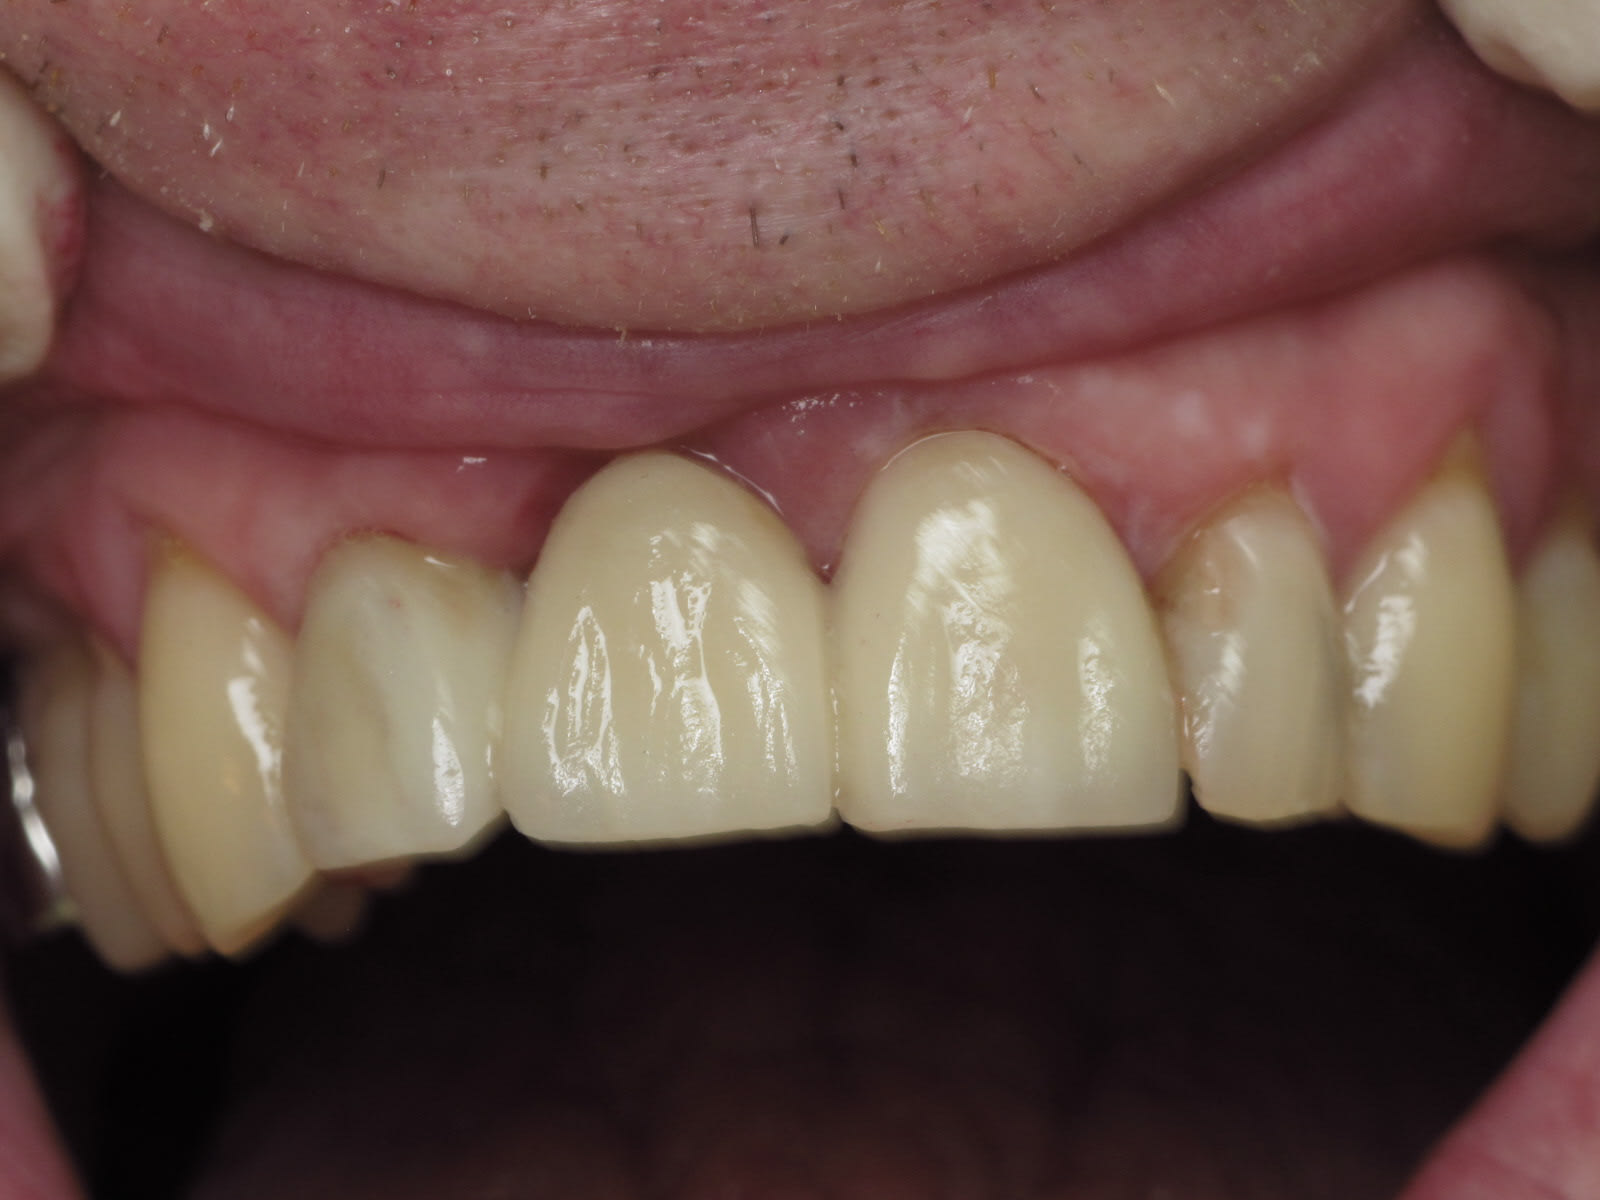

Hey ben bravo la compagnie ! C’est du propre !^^ Regardez moi voir vos bridges emax bande de vieilles branches -> ça n’a pas l’air d’être très solide.... du coup Implant plus prothèse provisoire

suite du chausse pied .

la séance d'après , lorsque tu déposes le prov ,le ciment prov reste sur le prov .

le sulcus ,qui n'avait pas saigné , est comme tu l'avais laissé , et il n'y a pas de surprise à l'essayage de la couronne .

avec cette stabilité tu en as pour des années ,je pense .

retour à l'envoyeur pour évaser un poil l'embrasure .